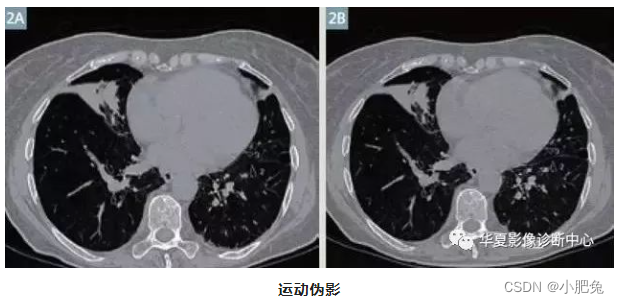

由于呼吸和心脏运动在胸部扫描中产生的运动伪影(图2A)。通过运动伪影校正算法改进后的图像(图2B)

运动伪影往往可设法避免, 对千呼吸和吞咽运动 , 可在检查前根据CT机的呼吸指令训练患者屏气, 告知患者尽量不做吞咽动作 , 并伸舌、 轻咬住舌尖, 不但可抑制吞咽动作, 还可避免舌根后坠, 影响会厌蹊的观察; 其次在一些运动器官的检查中, 尽可能采用缩短扫描时间, 缩短扫描时间是减少运动伪影最有效的方法 ; 第三可利用CT机上的一些运动伪影抑制软件进行处理, 可有效减少运动伪影。